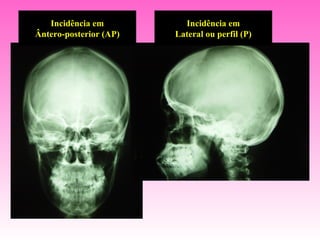

Incidência em          Incidência em

Ântero-posterior (AP)   Lateral ou perfil (P)